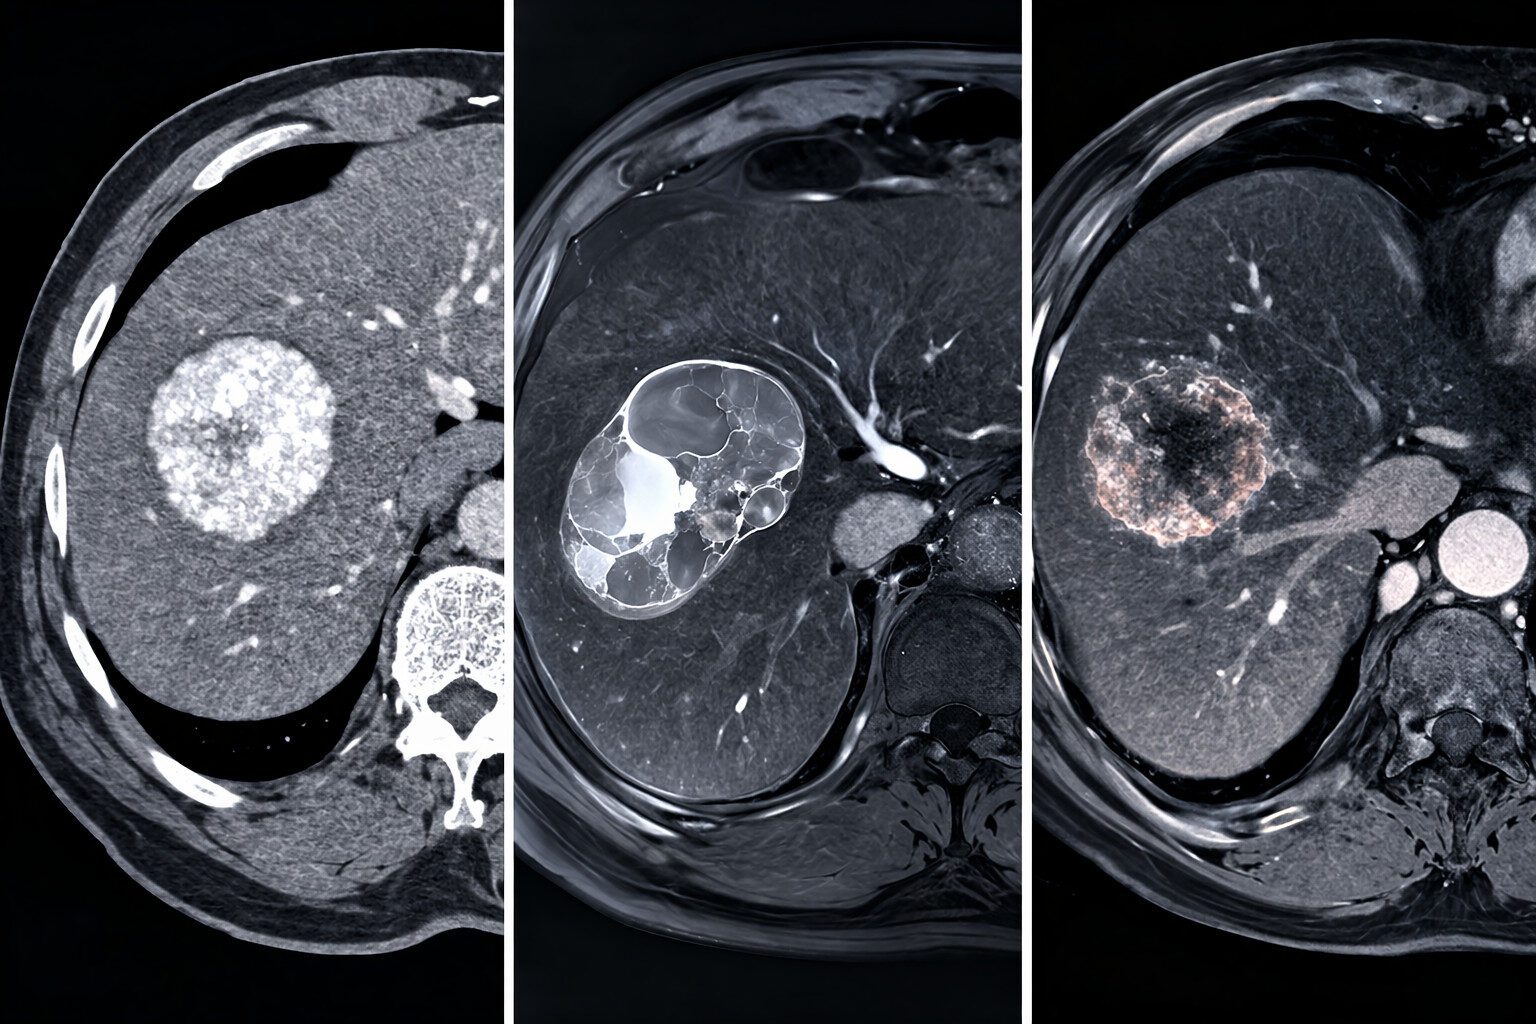

Leberläsion im CT/MRT – strukturierte Befundung und Differenzialdiagnose

Zufällig entdeckte Leberläsionen gehören zu den häufigsten Fragestellungen in der Schnittbilddiagnostik. Eine strukturierte Analyse in CT und MRT ermöglicht in den meisten Fällen bereits eine sichere Einordnung. Ziel ist es, benigne von potenziell malignen Läsionen zu unterscheiden und das weitere Vorgehen klar zu definieren.

Typische Differenzialdiagnosen

| Läsion | Typische Bildgebung | Kommentar |

|---|---|---|

| Zyste | Keine KM-Aufnahme | Benigne |

| Hämangiom | Peripher nodulär, langsames Auffüllen | Sehr typisch |

| FNH | Arteriell hypervaskularisiert, zentrale Narbe | Hepatobiliär hyperintens |

| Adenom | Heterogen, Fett möglich | Blutungsrisiko |

| Metastase | Randanreicherung | Immer Kontext beachten |

| HCC | Arteriell + Washout | Bei Zirrhose entscheidend |